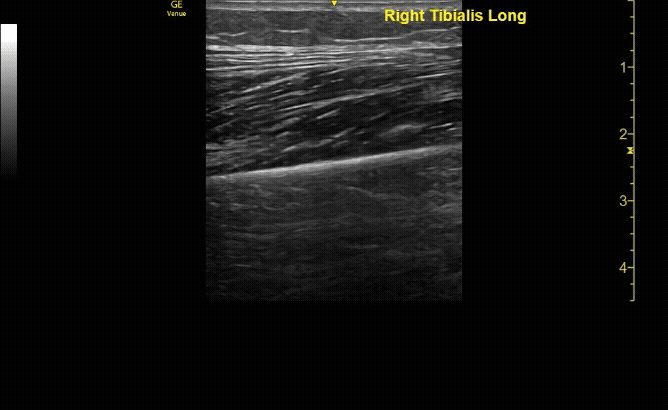

Unaffected tibia in sagittal view.

c/o Santiago Tovar, MD